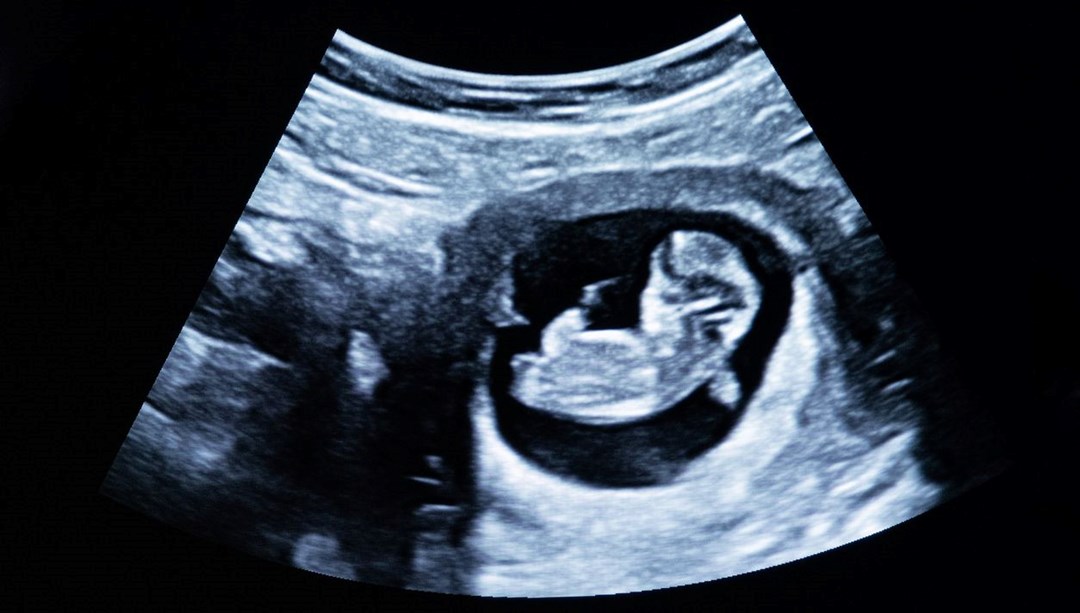

Yeni doğan bir bebek, kendi karnında gelişen iki fetüsle dünyaya geldi.

Bu, tıp literatüründe “Fetus in fetu” olarak adlandırılan ve dünyada yalnızca 200 kez kaydedilen son derece nadir bir anomali.

Kadın, 1 Şubat’ta sağlıklı bir erkek bebek dünyaya getirirken, doktorlar gelişimini tamamlayamayan iki fetüsü bebeğin karnından başarıyla çıkardı.

Taramayı gerçekleştiren Dr. Prasad Agarwal, “Karnında fetüs benzeri bir yapı bulunan, normal büyüyen bir bebek gördüm. Bu, dünyanın en nadir vakalarından biri” dedi.

“Fetus in fetu”, son derece nadir görülen bir tıbbi anomalidir. Bu durumda, bir fetüs anne karnında gelişirken, özdeş ikizi veya ikizleri tam olarak ayrılmaz ve onun içinde büyümeye devam eder. Genellikle gelişimini tamamlayamayan bu fetüs, konakçı fetüsün içinde parazitik bir şekilde varlığını sürdürür.

Bu durumun nedeni tam olarak bilinmese de, doktorlar bunun tek bir döllenmiş yumurtanın bölünmesi sırasında tam ayrılmamasından kaynaklandığını düşünüyor. İçeride sıkışan fetüs, zamanla tırnak, saç, uzuvlar gibi bazı yapılar geliştirebilir ancak hayati organları olmadığı için bağımsız olarak yaşayamaz.

Bu vakalar çoğunlukla fetüsün karın bölgesinde görülse de, bazen beyin, kuyruk sokumu, testis torbası veya ağızda da tespit edilebilmektedir. Dünyada yaklaşık 200 kez kaydedilen bu durum, tıp dünyasında büyük bir merak konusu olmaya devam etmektedir.